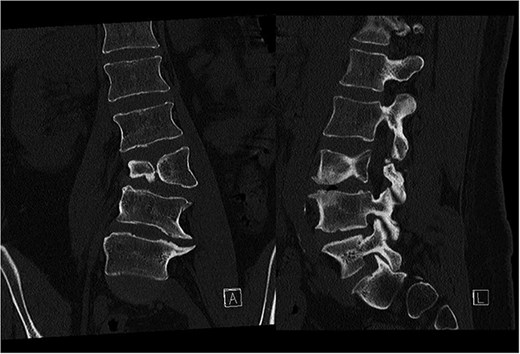

Last preoperative X-ray, lateral (A) and anteroposterior view (B). After 10 weeks of follow-up; lateral (C) and anteroposterior view (D). After 1 year of follow-up; lateral (E) and anteroposterior view (F).

CT-based 3D reconstruction revealed a semi-segmented hemivertebra at L3, resulting in a 32° Cobb angle of congenital scoliosis (Fig. 4). We decided to perform hemivertebra resection, L3 laminectomy, L2-L4 fixation with L3–4 cage fusion, and scoliosis correction. CT-based resection was 3D planned using EBS software (Fig. 6). Fixation from L2 to L4 was achieved using pedicle screws under fluoroscopic guidance, followed by L3 laminectomy. After accessing the L3–L4 disc space, a 3D real-time EMN-guided total resection of the L3 hemivertebra was performed (Fig. 6), and a cage with autogenous bone graft was inserted at the L3–L4 level. The left-sided L3 nerve was found to have an accessory branch, which was successfully preserved. Scoliosis was corrected using standard deformity correction maneuvers.

Postoperatively, the patient experienced left psoas and quadriceps femoris muscle paresis, with the latter gradually improved to near-normal before discharge. No other complications were observed. At the 10-week follow-up, the left quadriceps had regained full strength, but partial paresis (3 out of 5) of the psoas muscle persisted, resulting in gait disturbance. At the final follow-up, one year after surgery, imaging showed L2-L4 fusion with no signs of instability or residual deformity (Fig. 4). The patient’s back pain resolved. A normal muscle function was observed.